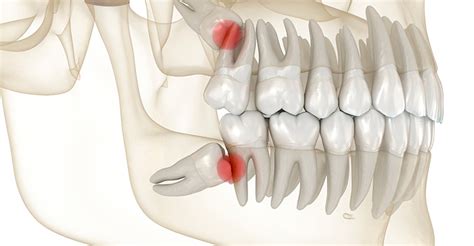

Lo más habitual es que la afección del “diente impactado” se dé en las muelas del juicio o cordales y en los caninos superiores. Esto se debe a que son las últimas piezas dentales en desarrollarse en las personas y se pueden encontrar con que las condiciones no son óptimas, debido a la falta de espacio al no desarrollarse adecuadamente los maxilares, infecciones bucodentales, una mala alimentación o por una predisposición genética.

Existen diversas razones por las cuales un diente queda impactado. Una de las más habituales es la falta de espacio en la mandíbula para que el diente pueda erupcionar correctamente. La falta de espacio o su inclinación durante la erupción es el motivo principal por el que un diente queda impactado.